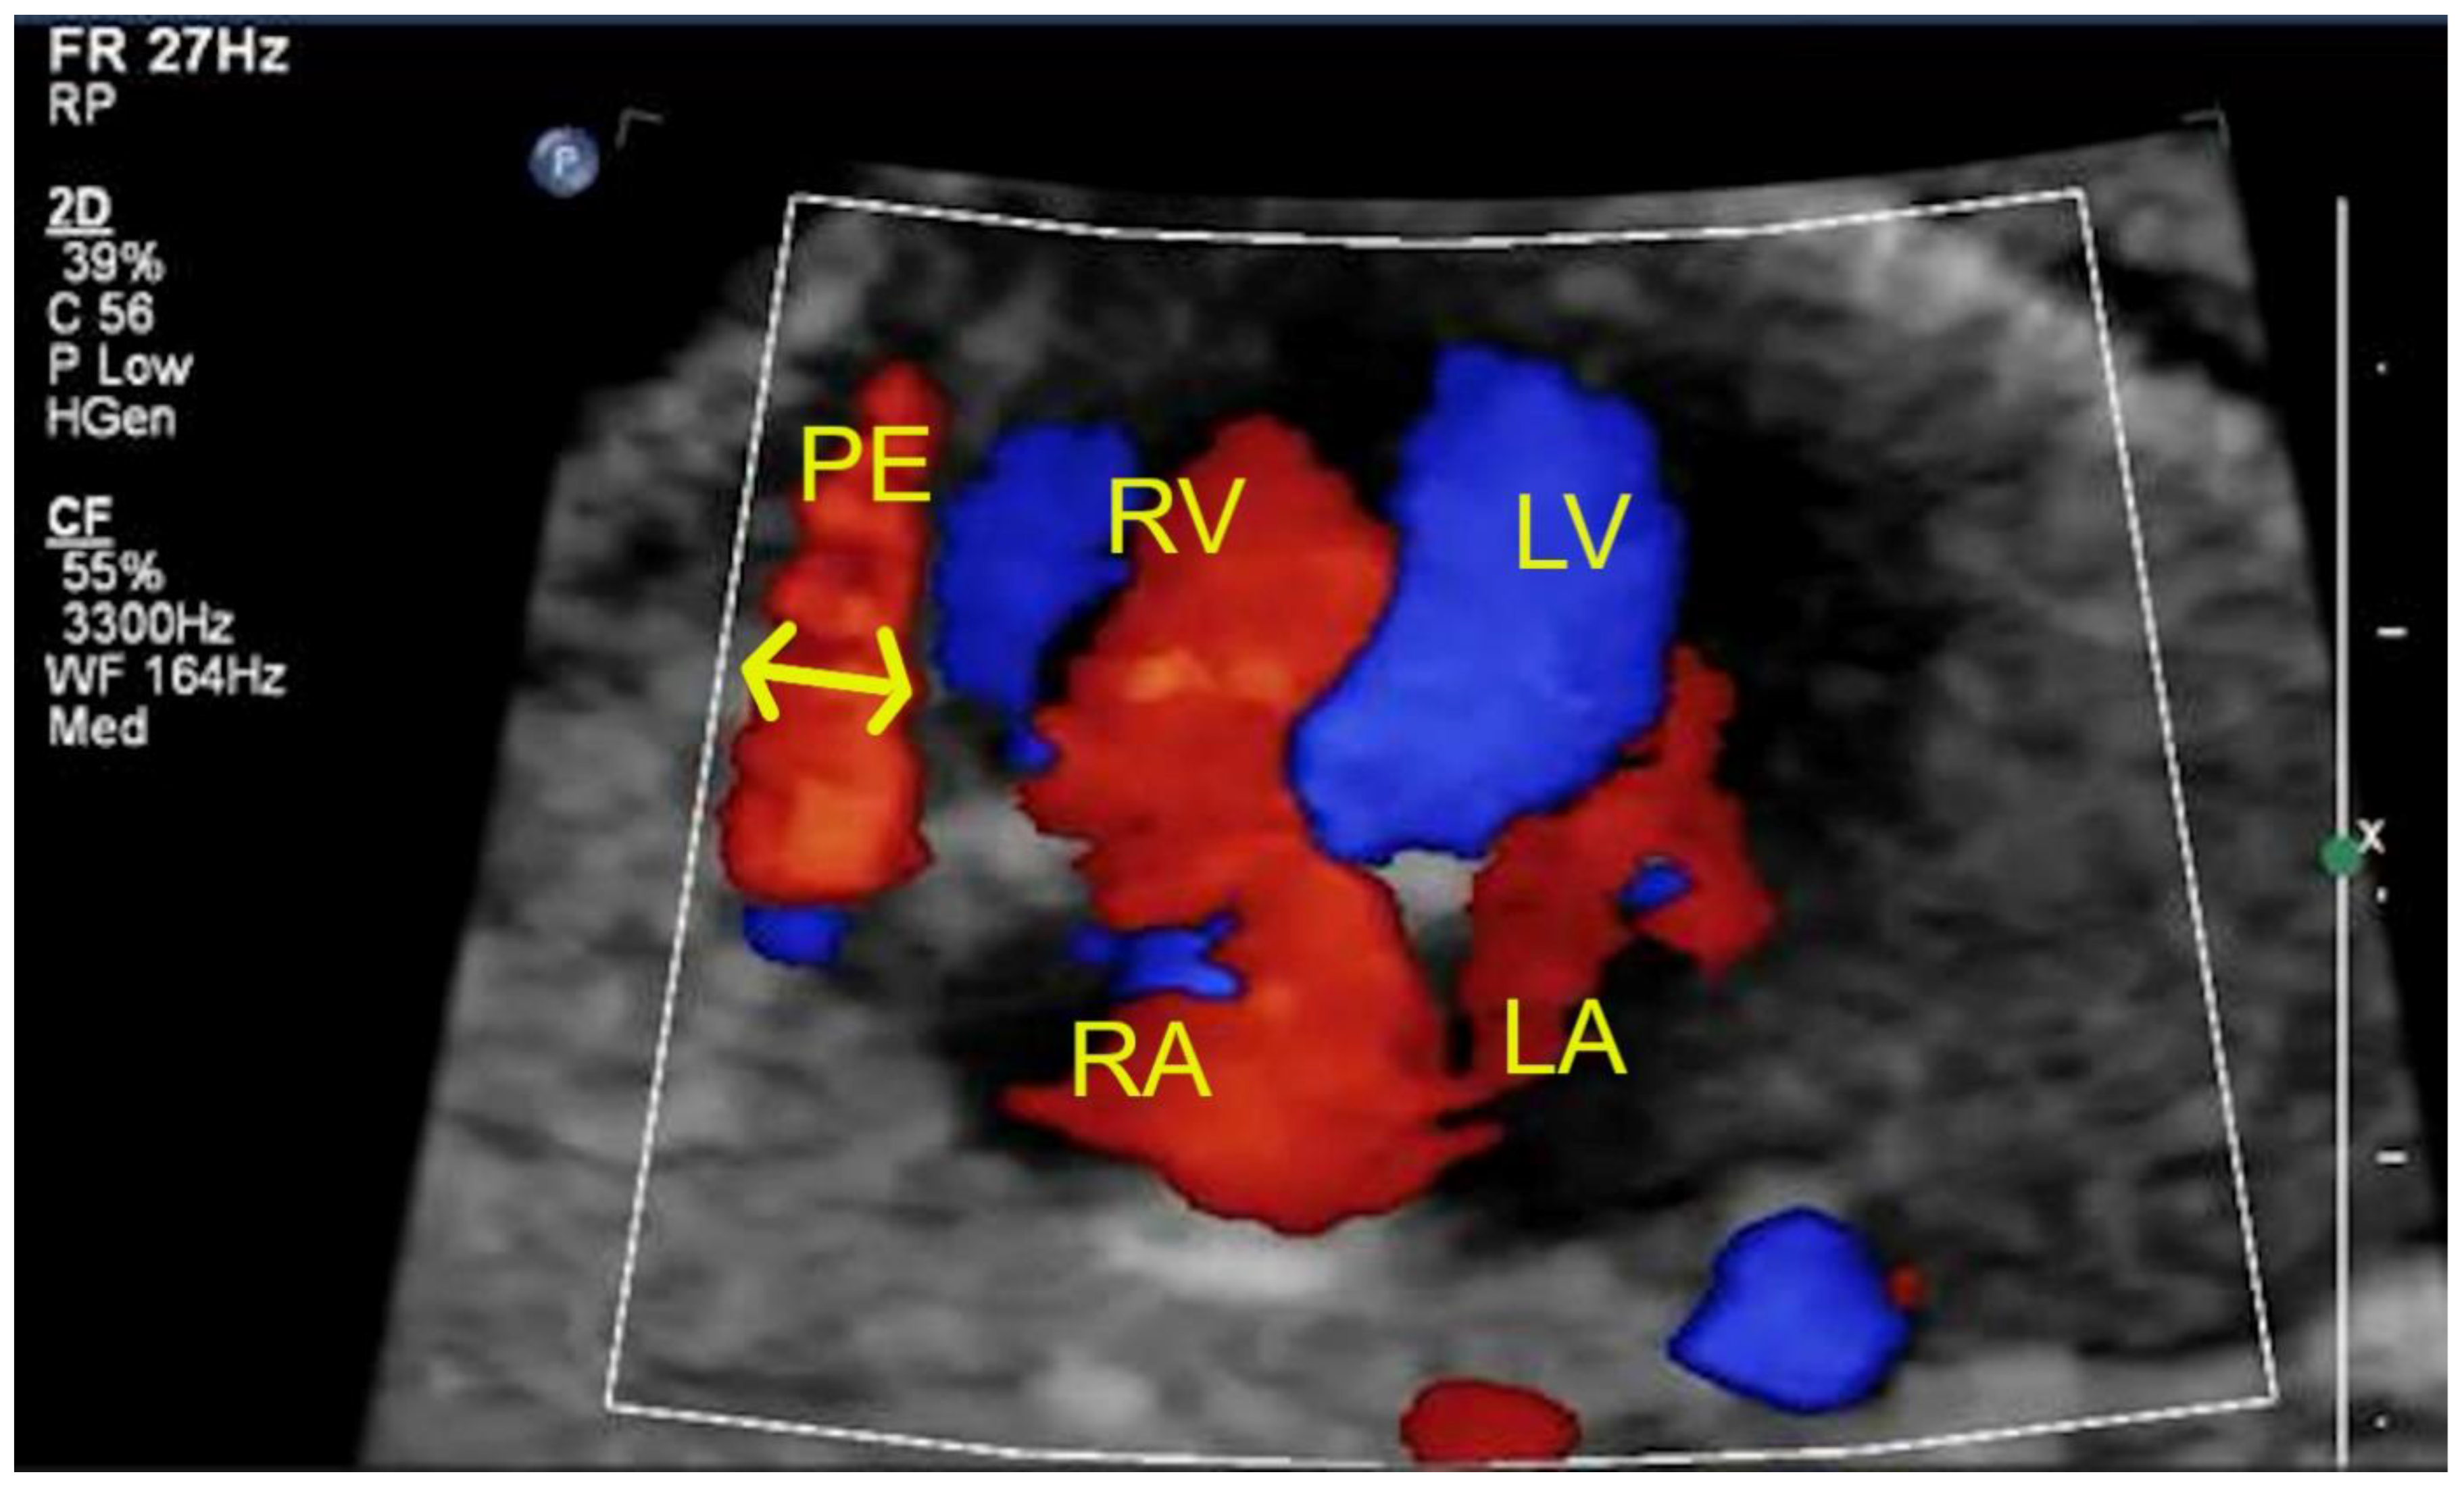

| Pericardial effusion (>2 mm) | 1 | 4 | - |